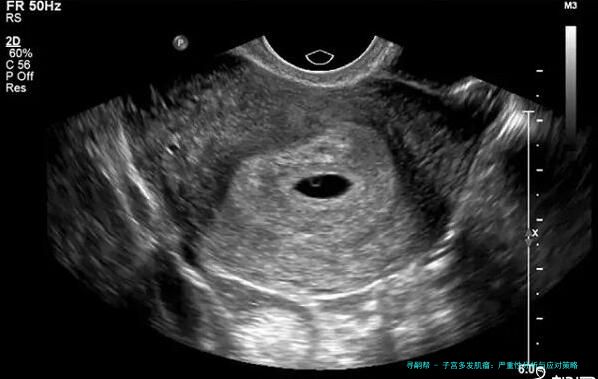

子宫多发肌瘤:严重性分析与应对策略

什么是子宫多发肌瘤?症状有哪些?

首先,子宫多发肌瘤简单来说,就是子宫里长了不止一个肌瘤。这些肌瘤是良性的肿瘤,由平滑肌和结缔组织组成,通常不会癌变。症状因人而异,有的人可能完全没感觉,而有的人则会经历月经量增多、腹痛、腰酸背痛,甚至影响排尿或生育。举个例子,我认识的一位阿姨,她就是因为月经期太长、量太大,才去医院检查,结果发现是多发肌瘤。医生说,这病在中年女性中更常见,但近年来年轻女性发病率也有上升趋势,可能跟生活压力大、饮食不规律有关。